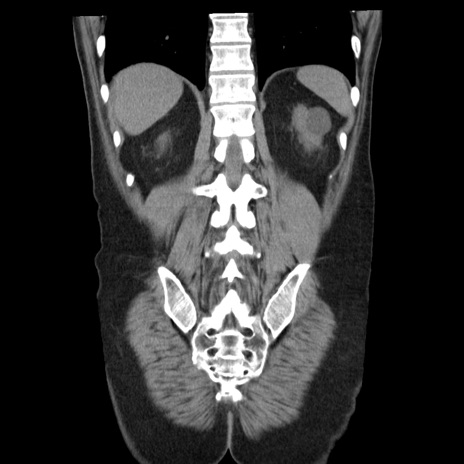

症例29(冠状断像)

【症例】40歳代男性

【現病歴】2日前から胃痛あり。徐々に周期的な激痛に変化した。本日になっても激痛があるため受診。

【身体所見】意識清明、BT 38-39℃台あり、腹部:膨満、やや硬、右下腹部に圧痛あり。

【データ】WBC 8500、CRP 23.26